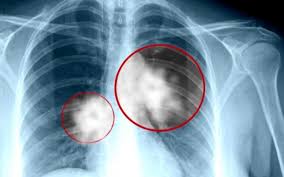

سرطان الرئة التشخيص والعلاج Mayo Clinic مايو كلينك

أخطر أعراض سرطان الرئة